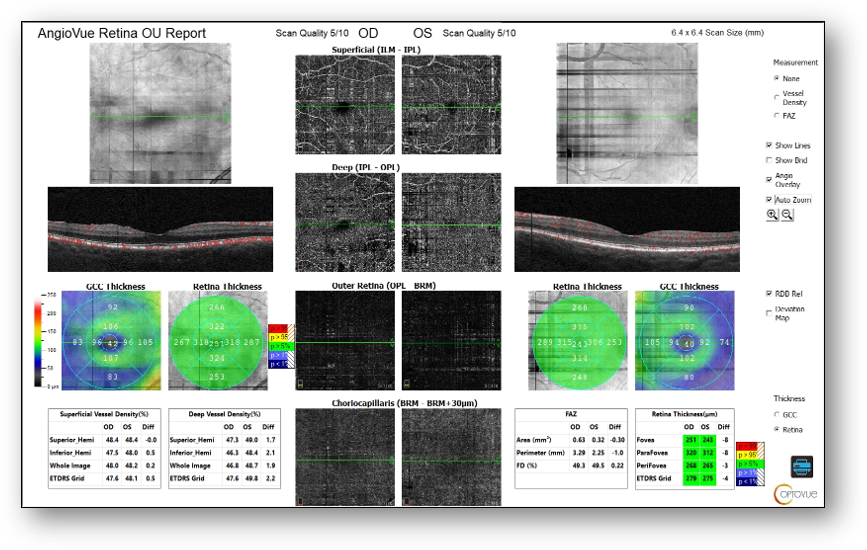

Fundus images showed small hard drusen throughout both maculae but no diabetic retinopathy (Figure 6). OCT revealed small drusen OU, mild ERM OD, and no diabetic retinopathy or macular edema (Figure 7). Notably, abnormal and asymmetric FAZ and capillary dropout OD > OS were found on OCT-A (Figure 8). These structural findings, combined with the patient’s poorly controlled diabetes secondary to medication unavailability were cause for concern and prompted me to perform ERG.

Figure 8: OCT-A